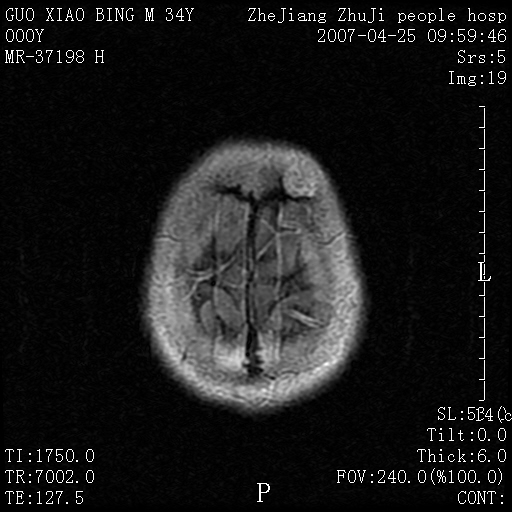

以下是引用qiuleiyu在2007-4-27 16:41:00的发言:[br]ct左侧额顶部囊性膨胀性骨质破坏,边缘有轻度硬化,其内示多发点条状高密度。[br]mri;t1低信号,t2明显高信号。界清。增强后明显强化。[br]综合考虑;颅内血管瘤。上传该病例,目的在于加深印象,共同学习。[br]骨血管瘤好发于颅骨及椎体。为良性肿瘤。组织学上分海锦型及毛细血管型。前者多见。[br]颅血管瘤典型影像学表现;[br]1,平片;类圆形骨质破坏,边缘硬化,内示中央向周边年轮状辐射(残存增粗骨小梁)。[br]2,ct;颅内板障内膨胀骨质破坏,边缘硬化,内示密集点状及放射状骨针影。[br]3,mr;t1、t2高信号。该病例t1不高可能与血流较丰富有关。边缘低信号。增强明显强化。[br]鉴别;[br]1,脑膜瘤;主要累及内板,与血管瘤发生于板障不同。颅板骨质增生硬化,与颅内垂直放射状骨针。与血管瘤日光放射状不同。增强可见脑膜尾征。[br]2,嗜酸性肉芽肿;起自板障溶骨性骨质破坏。内无点状及放射状高密度影。边缘硬化不明显。局部可有骨膜反应。[br]3,转移性肿瘤;溶骨破坏边缘模糊,无硬化边。发展迅速。有原发肿瘤史。可多发。可出现软组织块。[br]4,单发骨髓瘤;发病年龄较大,临床可能全身骨质疏松,骨痛。免疫球蛋白增高。部分病例本周氏蛋白可增高。可有边缘硬化,然内无点状高密度影。[br]